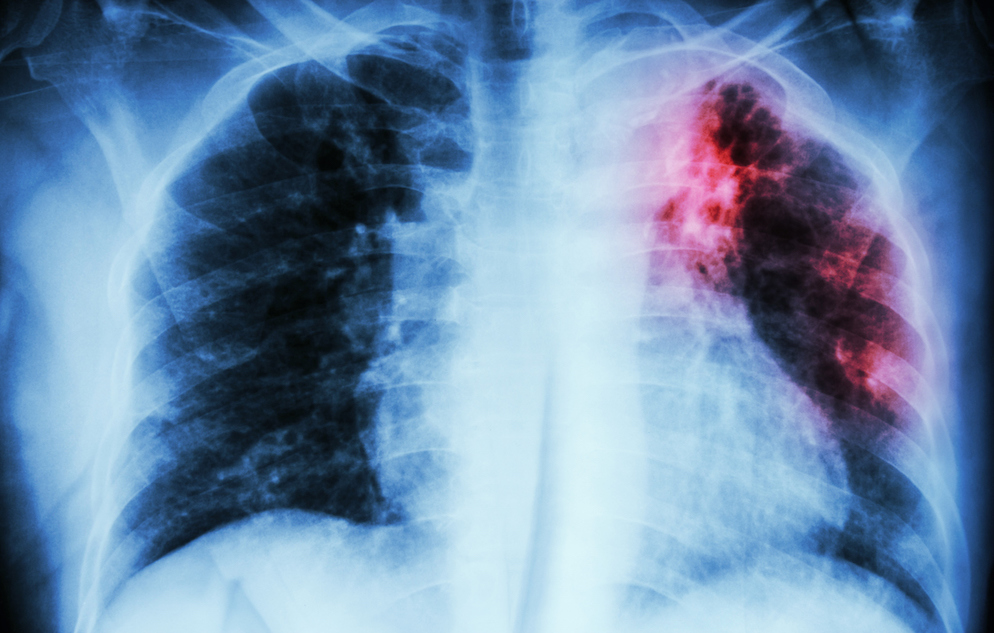

Tuberculosis (TB), which causes an estimated 1.5 million deaths around the world annually, continues to be an urgent global health priority. The high burden of mortality attributed to TB persists despite the long-term availability of the bacillus Calmette-Guérin (BCG) vaccine, whose efficacy has varied greatly across populations. Recent trials of other TB vaccine candidates, designed to boost the efficacy of BCG, have shown similar variability in efficacy from one population to the next. This inconsistency of biological response to the vaccine has also been observed in malaria and HIV vaccine development, where vaccine candidates appear to be highly effective in early phase trials, then perform below expectation in efficacy trials.